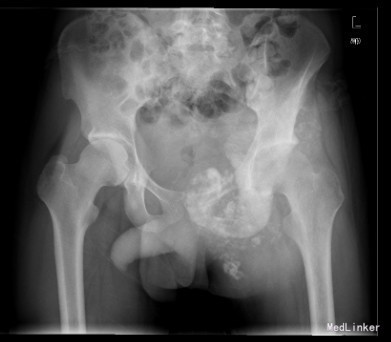

患者男,22岁,因“左臀部包块伴疼痛,进行性增大8+月”入院。入院前8+月,患者无明显诱因出现左臀部疼痛,并发现局部有包块。疼痛为钝痛,坐时加重,常反复,不伴发热及盗汗。于当地医院就诊,怀疑骨盆肿瘤;现为求进一步诊疗来我院就诊。

查体:左侧臀部内侧区隆起,局部皮肤无充血红肿,无浅静脉怒张,无皮肤破溃、皮疹及足癣。左侧臀部内侧区及左侧腹股沟区可触及巨大圆形包块,质硬,压痛明显,皮温不高,无明显触觉减退区,左足背动脉搏动正常,肢端末梢血循环正常。 辅查:骨盆CT提示左髂骨恶性肿瘤,突破皮质,边界不清,部分钙化。

初步诊断:左侧骨盆骨肉瘤(Ⅰ+Ⅱ+Ⅲ区) 诊疗计划:完善术前抽血常规、心电图及胸片等检查后择期手术治疗。